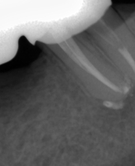

В стоматологической клинике "5 Принципов" в Симферополе мы гордимся тем, что каждый пациент получает индивидуальный подход и безупречный результат в области эндодонтического лечения под микроскопом. Наши специалисты применяют современные цифровые технологии, микропроцессорные и нейромодуляционные инструменты, что позволяет достичь максимальной точности и минимального дискомфорта. В портфолио клиники — широкий спектр кейсов: от первичной диагностики пульпита до сложной ретенированной резорбции и повторной эндодонтии. Мы беремся за зубы любых степеней сложности: от моляра до резцов, используя щадящие концевые инструменты и безболезненные методы постоянной анестезии. Все процедуры проходят под увеличением, что обеспечивает точное удаление инфицированной ткани и сохранение естественной анатомии зуба.Особое внимание мы уделяем постпроцедурному наблюдению: контроль за герметичностью заполнения корневых каналов, профилактические рекомендации и возможная корректировка плана лечения при необходимости. В "5 Принципах" мы разумно сочетаем комфорт, эстетическую привлекательность и долгосрочную функциональность. Результат — здоровые зубы, уверенная улыбка и спокойствие наших пациентов в Симферополе. Запишитесь на консультацию и убедитесь сами в нашем подходе к качественному эндодонтическому лечению.